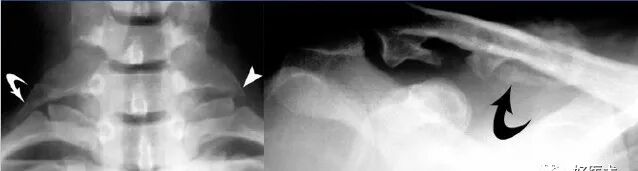

(二)病理 神经受压损伤常为假炎性肿胀样,感觉纤维最先受累,运动神经仅在晚期出现受压。此症状严重,较难恢复。神经受压时间过久则会通过交感神经导致血管舒缩障碍。锁骨下动脉血管壁可发生改变,动脉外膜增厚,间质水肿及同膜增厚伴管腔内血栓形成。早期血栓为纤维素血小板型,可出现雷诺(Raynaud)现象。 交感神经纤维收缩反射可加重指尖血管阻塞。 静脉在过度外展或内收时受到压迫,可观察到血液逆流停滞和外周静脉压上升,压迫消失后恢复正常。静脉壁反复损伤可发展类似炎症后纤维化样改变,静脉呈白色,失去半透明状态,且口径明显减小,形成侧支循环。早期发展趋势为静脉血栓,如侧支循环尚未形成,则可引起指端坏死改变。 临床表现 临床表现常见于中年妇女,20~40岁占80%,多有颈部外伤史。临床症状差异很大,且不持续 。分为神经受压和血管受压两类,神经受压的症状较为多见,也有神经和血管同时受压。 神经受压症状:有疼痛,感觉异常与麻木,常位于手指和手的尺神经分布区,也可在上肢、肩胛带和同侧肩背部疼痛并向上肢放射。晚期有感觉消失,运动无力,鱼际肌和骨间肌萎缩,4~5指伸肌麻痹形成爪形手。 臂丛神经受压:臂丛神经以跨越第1肋骨的下干最易受压,上干受压的较少,主要表现是臂丛神经下干受压的症状。 病人主要表现为:患侧肩部及上肢疼痛,无力,发病早期疼痛为间歇性,可向前臂及手部尺侧放射,肩外展及内旋时疼痛加剧。严重者可出现前臂及手部尺侧的感觉异常,甚至出现肌肉瘫痪,肌肉瘫痪及萎缩以小鱼际及骨问肌为甚,表现为爪形手畸形,有时也存在大鱼际肌及前臂肌肉肌力减退,锁骨上区有压痛并向前臂放射。 血管受压:一般病人不出现严重的血运障碍,当病变刺激血管时,可出现上肢套状感觉异常,患肢上举时感发冷,颜色苍白,桡动脉搏动减弱,锁骨下静脉严重受压时,则出现患肢远端水肿,发绀。血管严重受压时可出现锁骨下血管血栓形成,肢体远端血运障碍。 病史及症状: 既往史:大多数患者均有较长健康搜索的颈肩痛病史。 主要症状:本病的主要表现为颈肩部酸痛和不适,可向肩肘部放射患肢无力健康搜索,患者睡觉时患肢怎么放也不舒服可伴有头晕、耳鸣等症。 首诊时间:约30%的病例是在发病1年之内来诊,半数患者在1~2年来诊,另有20%患者超过2年来诊。 发病肢体:以非优势手多发,占2/3以上。 发病特点:急性发病者占55%慢性发病约占45%。 疼痛性质:均与体位关系密切,95%的患者呈间断性发作。 其他症状:几乎全部病例均有颈肩背部的异常、不适感约半数伴有疼痛。此外几乎95%的病例在睡觉时感到患肢怎么放也不舒服,同时伴有肩上举无力,少数患者可出现耳鸣、头昏及屈肘无力感。 诊断及鉴别诊断 1.诊断: 根据病史、局部体检、胸部和颈椎X线摄片和尺神经传导速度测定,一般可以明确诊断。 由于TOS患者临床表现复杂,与多种神经卡压症(如肘管)及运动神经元性疾病等症状相似,因此一种检查方法无法满足需要。 皮肤痛阈试验和两点辨别试验用于对中、晚期病人的诊断。而症状激发试验是最主要的早期诊断方法,包括“艾德森氏”试验、“过度外展”试验、“锁骨上叩击”试验、“上臂缺血”试验等。 1)“艾德森氏”征 病人端坐,双手置于膝上,将头转向患侧,下颌抬起使颈伸直,嘱病人深吸气后屏气,如桡动脉搏动减弱或消失者为阳性 2)“过度外展”试验 病人取坐位,检查者一手触摸病人桡动脉,同时将上臂被动地过度外展,如桡动脉搏动减弱或消失,腋下出现杂音者为阳性。 3)上臂缺血试验(一般认为最可靠) 即患者双上臂抬起,前臂屈曲90°,肩外展外旋,交替握拳与松开,若3min内一侧产生疼痛或不适而被迫下垂为阳性。 2.影像学 胸廓出口综合征主要依赖临床特征诊断,影像学有助于了解受压部位,解剖特征,确定手术方案:影像学检查X线颈椎片和胸片可以排除颈肋、第7颈椎横突过长、锁骨、第一肋骨畸形或其它骨性病。 平片——骨质异常 平片可以排除骨性结构的异常,图中两人都是临床证实的胸廓出口综合征的病人。 左图可以发现病人存在第七颈肋及颈七椎体横突过长; 右图则是锁骨骨折后骨痂过度形成而导致的肋骨锁骨间隙狭窄。 多普勒超声可以发现血管受压狭窄,血管造影可以确定狭窄和受压的部位: 评价动脉受压病变 静脉受压评估欠准确 臂丛显示不清 CT血管造影可用于评价动脉受压病变,图来自一个37岁的男性,图a是正常状态下的矢状位,锁骨下动脉没看到明显受压,图b是该病人手臂外展时的矢状位图,可以看到锁骨下动脉受压变窄,图cVR图直观显示血管跟周围骨骼结构的关系。值得注意的是,影像学对于静脉受压的评估相对欠准确,因为即使在正常人手臂外展时也会引起静脉受压,CT血管造影一个明显的缺点是对臂丛显示不清。 CT和MRI是一种敏感且无侵害性的方法,对TOS的确诊有一定帮助。 MRI--矢状位T1WI评价血管神经压迫最准确。 MRI可以准确观察与胸廓出口综合征相关的所有解剖结构,文献报道T1WI最有利于评估相关结构改变。这两幅图展示的是冠状位及轴位的T1WI图像。要注意的是,正常臂丛结构在所有序列上均为低信号。 相对于冠状位及轴位,矢状位对于评价血管神经压迫最准确。这是一个四十七岁的女性,左图是上臂外展前的T1WI矢状位图,臂丛没有受到明显压迫,而右图是上臂外展状态下的矢状位图,可以看到原先的结构明显受压。 电生理检查在TOS的早期无特殊价值,可能会出现F波延长,其它常常无异常发现。 晚期如尺神经运动传导速度在锁骨部减慢有较大的诊断价值。分别测定胸廓出口,肘部,前臂处尺神经传导速度。 正常胸廓出口为72m/s,肘部55m/s,前臂59m/s。胸廓出口综合征病人胸廓出口尺神经传导速度减少至32~65m/s,平均为53m/s。 3.辅助检查 上肢外展试验:上肢外展90°,135°和180°,手外旋,颈取伸展位。使锁骨下神经血管紧束压在胸小肌止点 下方和锁骨与第1肋骨间隙处,可感到颈肩部和上肢疼痛或疼痛加剧。桡动脉搏动减弱或消失,血压下降。 4.鉴别诊断 1)颈椎病 亦可出现上肢疼痛、无力、感觉异常,但颈椎病病人颈部常有压痛,压头试验及臂丛神经牵拉试验常为阳性。x线片有颈椎骨刺增生,椎间隙变窄,钩椎关节改变等退行性变的表现,CT及MRI可显示椎间盘变性及神经根、脊髓受压。 2)肘管综合征 为尺神经在肘管内受压所产生的临床综合征,表现为手无力,患肢手部尺侧感觉异常,小鱼际及骨间肌萎缩,爪形手,与本病主要累及尺神经所产生的临床表现相似,但前者无肩部症状,不波及正中神经,体征局限于肘部以下,AdSOn征、wright征、ROOs征等特殊试验阴性。 3)腕管综合征 为正中神经在腕管内受压所致,主要表现为手部桡侧2/3及桡侧3个半手指的感觉障碍,拇指对掌功能障碍,通过临床症状及检查,不难鉴别。 治疗 1.非手术治疗